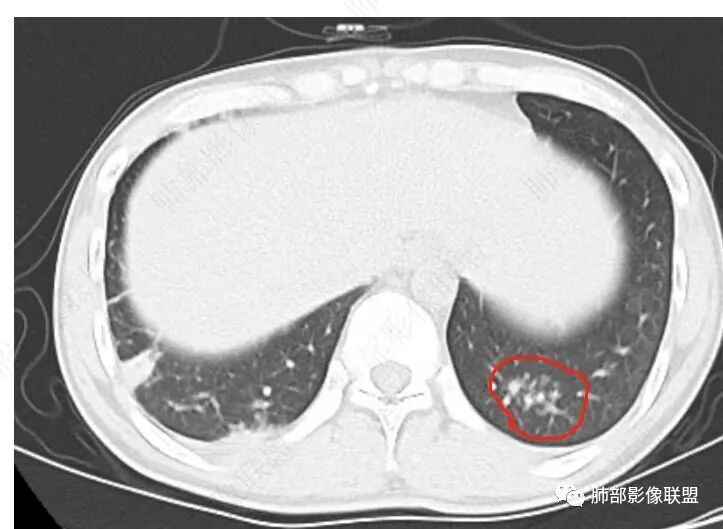

两肺多发结节及团块,沿支气管血管及胸膜下分布,部分融合,星系征,增强延迟强化,两肺门及纵膈淋巴结肿大,考虑结节病

星系征+纵隔肺门孤立性淋巴结肿大,支持结节病,鉴别结核

双肺多发实变,边缘见平直及u型凹,实变周围多发弥漫粟粒结节呈星系征样改变,轻度强化,实变内可见血管影,双肺门及纵隔淋巴结肿大,肿大淋巴结无融合,年轻患者,无TB中毒征状,首选结节病

这是小叶核心结节的特点

小叶核心的:小气道一-树芽征,淋巴道、血道、气腔都可以

2.影像特点:双肺多发实变,结节状、斑片状、斑点状影,成簇分布趋势,密度不均(部分密度较高),多数位于胸膜下或支气管血管束周围,与支气管关系密切,部分气管壁钙化,部分实变影周围多发弥漫粟粒结节呈星系征样改变,呈轻度渐进性强化,未见空洞。双肺门及纵隔淋巴结肿大,并显示融合,其中后纵隔肿大淋巴结间可见血管影穿行。右侧胸膜增厚伴少量胸腔积液。